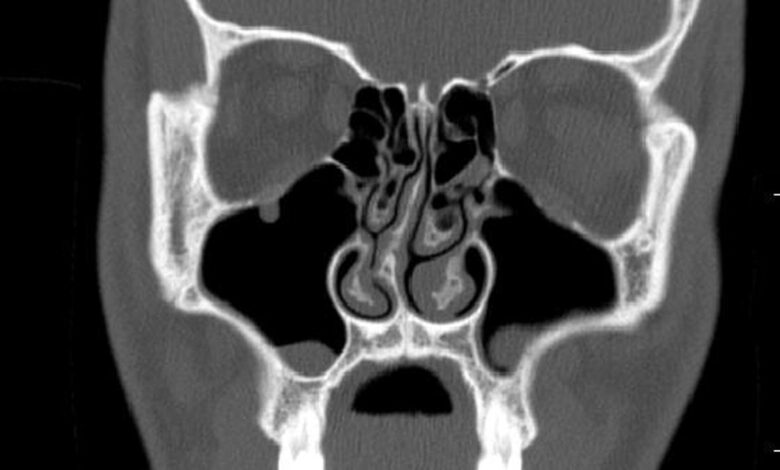

Pro diagnózu zůstává standardem klinické vyšetření. „Můžeme diagnostikovat ohyb pouhým vyšetřením a dále jej potvrdit buď endoskopickým vyšetřením nebo CT skenováním,“ říká Shruthi Sreekumar, přidružený konzultant, ENT, Rela Hospital, Chennai. V některých případech CT skenování paranazálních dutin pomáhá objasnit přidružené onemocnění.